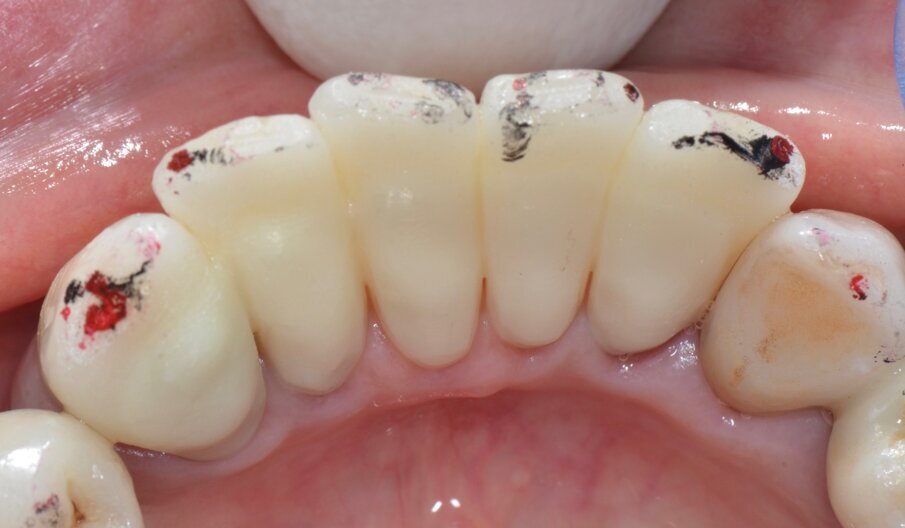

Riguardo al comparto intraorale, dalle radiografie diagnostiche e dall’esame parodontale e occlusale sono emersi aspetti che meritavano una correzione anche nei settori posteriori, ma la paziente ha deciso di effettuare inizialmente il trattamento dei soli gruppi frontali superiore e inferiore demandando a un momento successivo le problematiche dei quadranti posteriori (Figg. 2-6). Nel gruppo frontale superiore si possono notare recessioni gengivali sugli incisivi centrali, che sono anche molto ruotati, e sul canino di sinistra; corone in metallo-ceramica sugli incisivi laterali con esposizione del bordino metallico e una corona in ceramica metal-free sul canino di destra. Inoltre è molto evidente lo squilibrio delle parabole gengivali tra i due canini, per cui per ristabilire un’estetica ottimale sarà necessario anche interessare i tessuti molli eseguendo una chirurgia resettiva sul canino di destra e, al contrario, un lembo a posizionamento coronale sul canino di sinistra (Fig. 7).

Da un punto di vista protesico verranno eseguite corone singole in zirconia stratificata sugli elementi 13-12-11-21-22 e una faccetta in disilicato di litio sul 23. A causa della notevole rotazione dei due incisivi centrali in fase di ceratura abbiamo optato per due corone complete anziché due faccette per una migliore distribuzione degli spazi protesici dei quattro incisivi (Fig. 8). Il gruppo frontale inferiore invece verrà protesizzato con corone in zirconia stratificata sugli elementi 32-31-41-42-43 splintate per compensare una mobilità di grado 1 dei quattro incisivi.